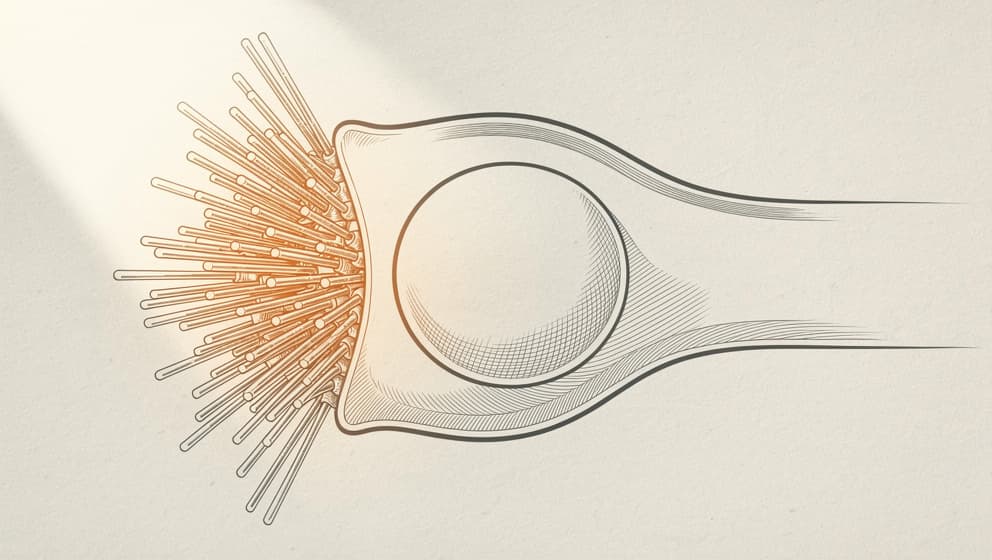

What TB-500 is#

TB-500 is a synthetic peptide corresponding to a 17-amino-acid active fragment of native thymosin beta-4 (TB4). TB4 itself is a naturally-occurring 43-amino-acid peptide found abundantly in platelets, wound fluid, and many other tissues. It plays roles in actin sequestration, wound healing, and cellular migration across multiple tissue types.

Manufacturers synthesize the shorter TB-500 fragment because it retains the key biological activity of full-length TB4 while being dramatically easier to produce and more stable in solution. For practical purposes TB-500 and "thymosin beta-4 fragment" refer to the same research compound.

TB-500's primary mechanism is actin sequestration. Actin is the cytoskeletal protein that gives cells their shape and powers their movement. TB-500 binds to monomeric G-actin, regulating the dynamic balance between G-actin and filamentous F-actin that cells need to migrate, divide, and remodel.